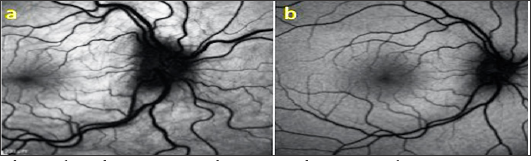

As a result of the examinations, traumatic cyclodialysis induced hypotoniamaculopathy was diagnosed for right eye. Topical corticosteroid and cyclopentolate therapy was initiated, and 3 days later the right eye axis was measured as 22,80 and the refraction rate was measured as +0,75. The IOP returned to 18 mmHg and the VA was 10/10. Comparing the OCT images taken at the end of treatment with the first received OCT, the choroid, RPE and wavy appearance of the retina (Figure 1a). Were seen to be healed at the end of treatment (Figure 1b). Cyclodialysis was detected in the temporal quadrant (Figure 2a). By UBM and normal culinary anatomy was obtained at the end of the treatment (Figure 2b). There was a normal appearance at the end of the treatment (Figure 3a), while significant increase in tortuosity was observed in vascular structures at the first examination of the FOF (Figure 3b).

Figure 3: a. Right-eye at first and treatment outcome, b. FOF images taken at 30° magnification.